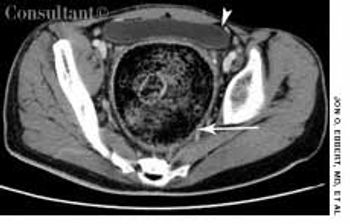

A 31-year-old man with a history of traumatic brain injury was hospitalized because of failure to thrive, constipation, and intermittent diarrhea with soiling.